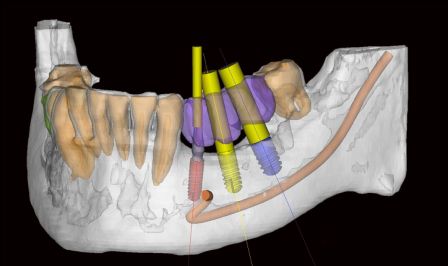

- Оценка расположения важных анатомических образований в области планируемой установки имплантов для исключения их травматизации.

- Виртуальное планирование и расстановка имплантов в специальной компьютерной программе для определения оптимальных размеров и позиций зубных имплантов. Это позволяет нам получить идеальную основу для будущего протеза, который будет опираться на устанавливаемые имплантаты.

Основываясь на полученных данных изучения компьютерной томографии и беседы с пациентом, мы можем успешно спланировать любую, даже самую сложную операцию по установке зубных имплантатов, максимально снизив риски возможных осложнений во время имплантации.